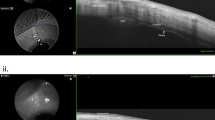

This study was set in Raghudeep Eye Clinic, Ahmedabad and LV Prasad Eye Institute, Hyderabad (India). It is a Prospective Case Series. Prospective case series comprising of patients with uncomplicated pseudophakia and CME due to IGS who recurred after one course of topical steroids with NSAIDS and a sub-Tenon corticosteroid injection. A complete ocular and systemic exam, fluorescein angiography, and central subfield thickness (CST) on optical coherence tomography scans were performed. Follow-up visits were on days 1, 15, and 30 and then monthly for a year. Appropriate statistical analysis was done. The primary outcome measure was the change in CDVA at months 1, 6, and 12. Secondary outcome measures were recurrence of CME and complications if any as noted at months 1, 2, 6, and 12.

About 27 patients (27 eyes) with 16 males were included. Median age: 63.24±5.62 years. At 1 month, the CDVA improved to 0.04±0.02 (20/25) logMAR from 0.52±0.12 logMAR (20/70) (P=0.001) with a reduction in CST from 454.2±45.3 to 218.32±38.15 microns(P=0.013). The CDVA was 0.04±0.03 logMAR(P<0.001) at month 6 and 0.05±0.02 logMAR(P<0.001) at month 12. The CST was 221±35.2 microns (P=0.013) at month 6 and 214±43.34 microns (P=0.0124) at month 12. All improvements were maintained for a year. Only one patient required a second injection. No complications were noted.